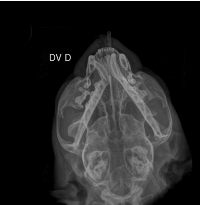

Oi pessoal… eu nunca imaginei precisar escrever isso, mas hoje estou pedindo ajuda para salvar o meu gatinho. Meu nome é Andressa e o Eren é meu companheiro, meu neném. Ele tem apenas 9 meses e sofreu um acidente que mudou tudo de repente. Levei ele às pressas para o hospital veterinário, onde chegou com dificuldade para respirar, muita dor e sangramento na boca, precisando ficar no oxigênio e ser internado imediatamente. Os exames mostraram que o impacto foi muito forte e causou uma luxação bilateral da mandíbula. Basicamente, a boquinha dele saiu do lugar dos dois lados. Desde então, ele não consegue fechar a boca direito, sente dor constante e não consegue se alimentar sozinho.Ver o Eren tentando comer e não conseguir é uma das coisas mais dolorosas que já vivi. Ele precisou passar por anestesia para tentar reposicionar a mandíbula e agora está com a boca imobilizada, usando focinheira por cerca de 20 dias e se alimentando através de uma sonda diretamente no esôfago. Mesmo assim, ainda existe a possibilidade de uma cirurgia mais complexa com ortopedista caso a mandíbula não permaneça no lugar. Foram dias de internação, exames, medicações fortes, monitoramento constante e cuidados intensivos, porque o trauma trouxe risco real à vida dele. Os custos estão aumentando a cada dia e infelizmente eu não estou conseguindo ter condições de arcar com tudo sozinha. Estou criando essa vaquinha porque quero dar ao Eren a chance de se recuperar e voltar a ter uma vida normal novamente e sem dor. Qualquer valor vai ajudar muito 🙏